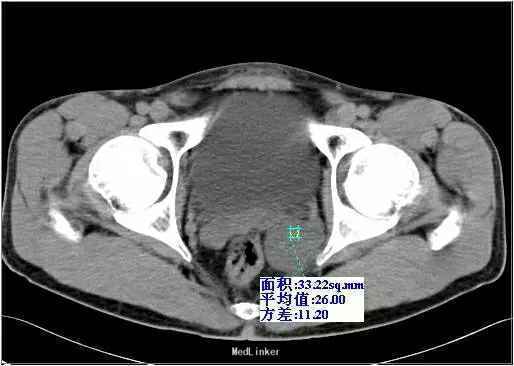

查体:左侧精囊区肿块,大小约3cm,质硬,活动度可,轻挤压痛,余体检无异常。实验室检查:血常规、生化、凝血、尿常规及肿瘤标记物化验未发现特殊异常。 影像检查:超声示盆腔内直肠中段左侧见一肿块图像,大小约4.4 cm×5.0 cm×3.2 cm,形状呈椭圆形,边界欠规整,内部为低回声,分布不均,后方回声无变化,彩色多普勒显示肿块内部可见少许点状血流信号。 CT示左侧精囊区见一肿块,大小约4.3 cm×3.6 cm;平扫呈稍低密度(相对邻近肌肉密度),密度不均,其内可见散在分布更低密度区,CT值约18-28HU,动脉期CT值20-28HU,静脉期CT值20-30HU,肿块边缘规整、边界清楚,与直肠膀胱分解清楚。